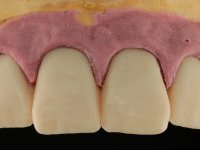

O paciente foi observado conjuntamente e a dúvida que surgiu de imediato foi se seria possível com a regeneração óssea a efectuar poder ser reabilitada naturalmente a zona das papilas interdentárias. Nesse sentido foi feito um enceramento de diagnóstico que contemplaria as duas hipóteses, utilizando ou não a cerâmica gengival. A confecção desse enceramento foi fundamental para expor ao paciente a dificuldade da reabilitação. O wax-up deu origem a um mock-up que foi aprovado pelo paciente e que simultaneamente serviu de guia imagiológica. O caso foi planificado cirurgicamente e realizada uma guia cirúrgica com que foram colocados os implantes. Após 10 semanas foi feita a 1ª impressão para confecção da ponte provisória. Foram criados os primeiros perfis de emergência na gengiva artificial e foi digitalizado o modelo. Por processo de CAD-CAM foi confeccionada uma ponte provisória aparafusada baseada no enceramento de diagnóstico. A ponte trabalhou durante 8 semanas os tecidos moles que foram fielmente copiados numa impressão com técnica de moldeira aberta. Os transferes foram individualizados com resina composta para copiarem fielmente os perfis de emergência criados pela ponte provisória. Confeccionado o modelo de trabalho definitivo, foi realizada uma infra-estrutura em zircónio seguindo a orientação do enceramento de diagnóstico. O assentamento da infra-estrutura foi testado em boca e simultaneamente foi novamente impressionados os tecidos moles com um silicone fluido. Nessa consulta foi feito o levantamento da cor. Os dentes 13 e 23 apresentavam uma saturação anormalmente forte que resolvemos não valorizar, optando por privilegiar a relação com o sector antero-inferior. Foi realizada uma nova gengiva artificial com a impressão que acompanhou a impressão de arrasto com a infra-estrutura. Após a colocação da cerâmica na infra-estrutura foram coladas as meso-estruturas. O trabalho final foi aparafusado lentamente permitindo a adaptação dos tecidos moles.